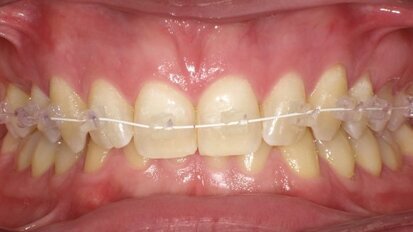

Nuovi traguardi ortodontici al servizio dell’estetica

In risposta alla sempre più frequente richiesta da parte dei pazienti in termini di estetica del sorriso, assistiamo oggi ad un’ulteriore evoluzione dei ...

Protocollo sperimentale per la gestione dei tessuti duri durante il trattamento ortodontico

L’ortodonzia è la branca dell’odontoiatria che si occupa di prevenzione, diagnosi e trattamento delle alterazioni scheletriche a livello del massiccio ...

Approccio terapeutico combinato sbiancamento e Infiltrazione Icon della White Spot Lesions (WSL)

La presenza sulle superfici dentali di White Spot Lesions crea disagio nel paziente poiché inficia la bellezza di un sorriso. Il termine White Spot Lesions...